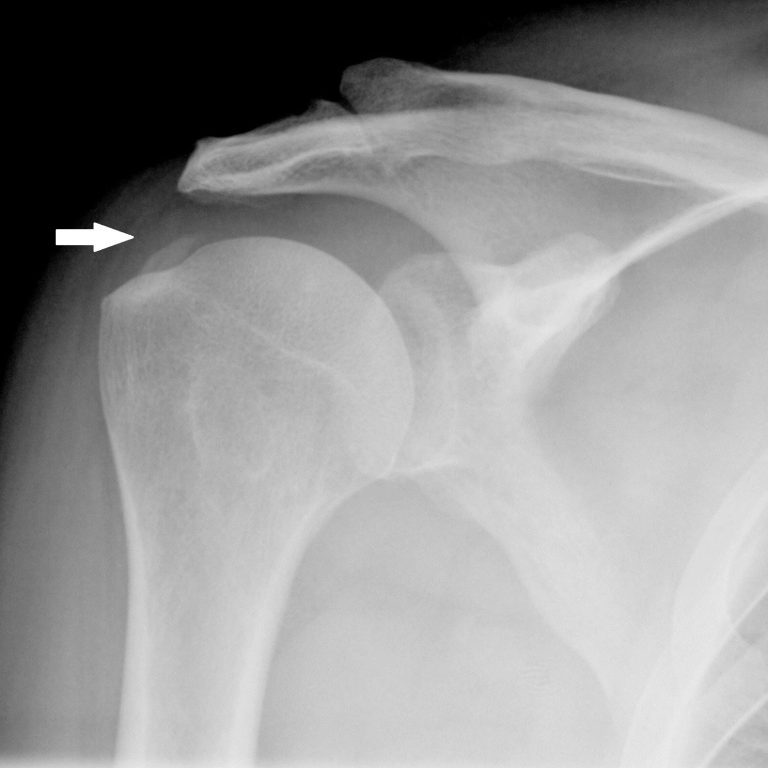

Überlastungsschäden

Sehnenansatzbeschwerden wie Tennis- und Golferellenbogen, Kalkschulter, Fersensporn, Patellaspitzensyndrom.